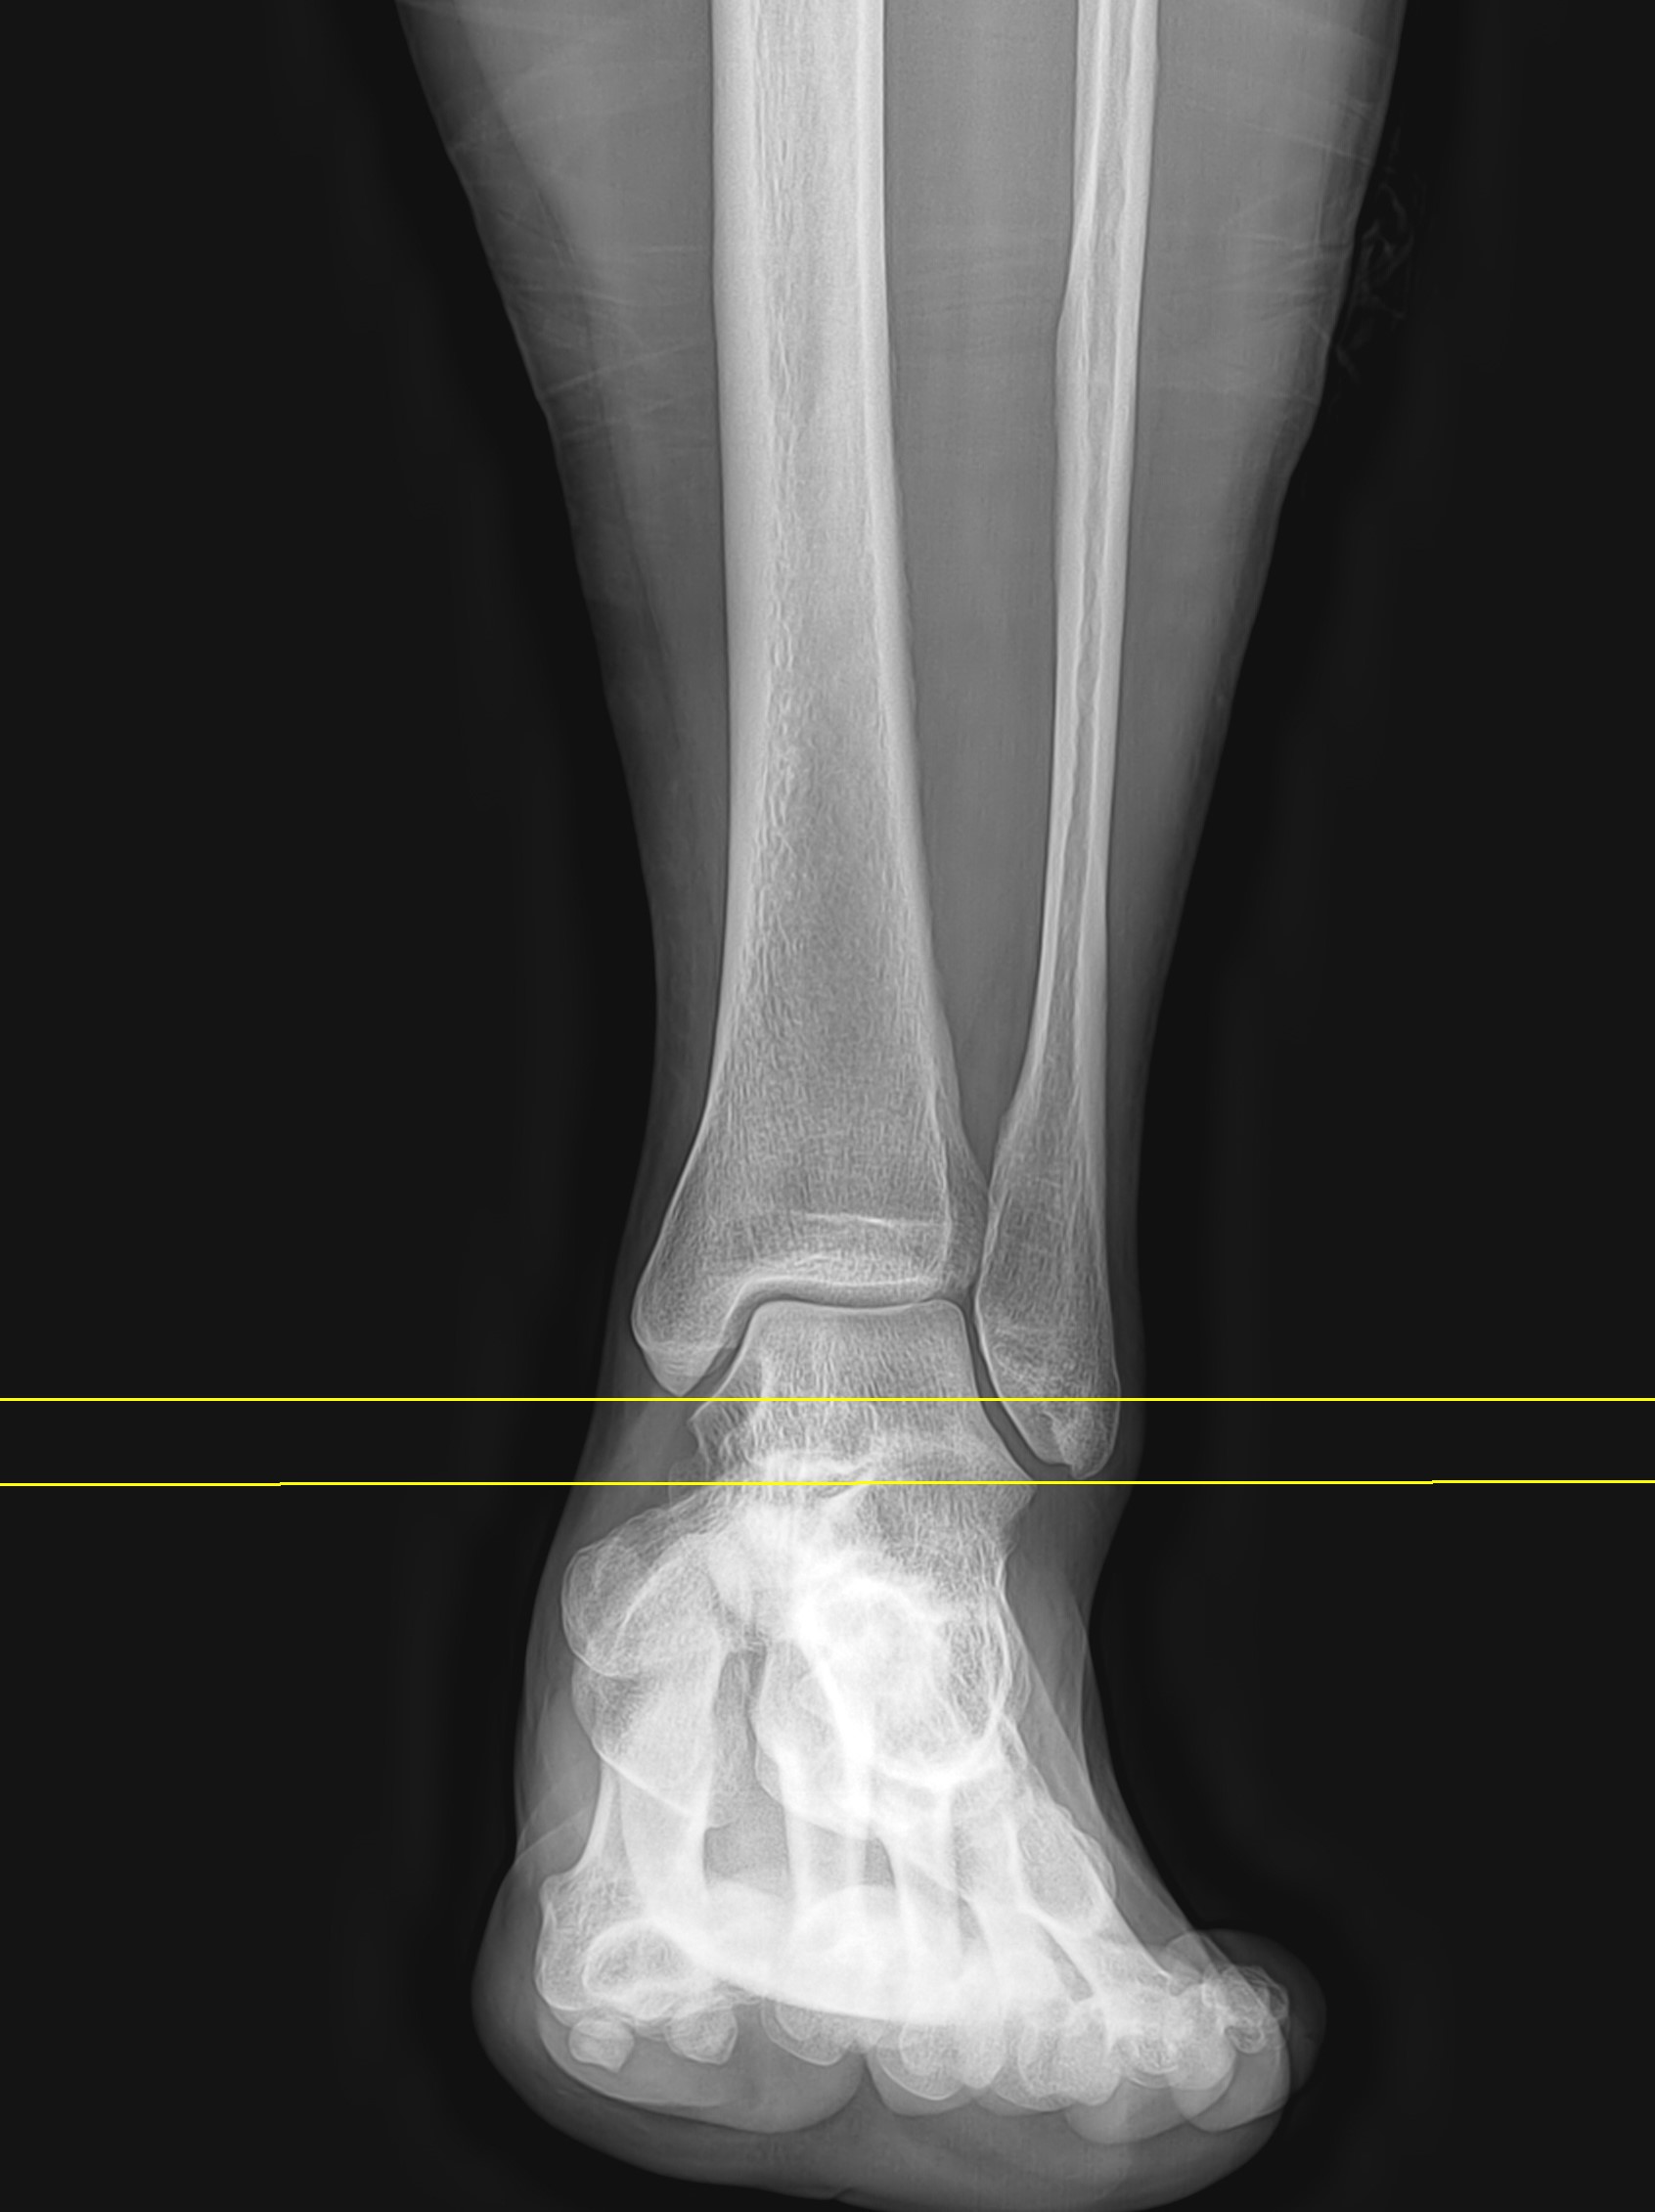

본원에서 내원한 13세 암자 환자로, 농구하다가 발목을 심하게 접질렸는데, 다쳤을 당시 발목 외측이 심하게 멍들고 부었다고 하였습니다. 2주 동안 한의원에서 침만 맞고 지켜봤으나 통증의 호전이 없어서 내원을 한 경우였습니다.

진찰 당시 멍은 다 빠져있었으나 약간의 붓기는 남아있었으며, 발목 외측 부위의 압통이 명확히 있었고, 반대측에 비해 발목이 약간 흔들리는 불안정성을 보이고 있었습니다. 발목 엑스레이 검사와 초음파 검사를 바로 시행했응며, 발목 외측 인대 중 2개의 파열 소견이 관찰되었습니다. 파열된 인대는 가장 흔하게 손상되는 1,2위 인대로 전거비인대(Anterior talofibular ligament)와 종비인대(Calcaneofibular ligament)의 거의 전층 파열이 확인되었습니다.